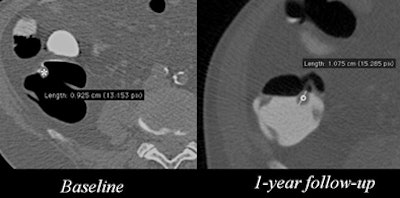

| Patient had a subcentimeter polyp in the ascending colon that grew to more than 1 cm after one year. Image courtesy of Dr. Lorenzo Faggioni. |

The study aimed to evaluate patients' preferences about follow-up of 6- to 9-mm polyps detected at screening virtual colonoscopy (also known as CT colonography or CTC).